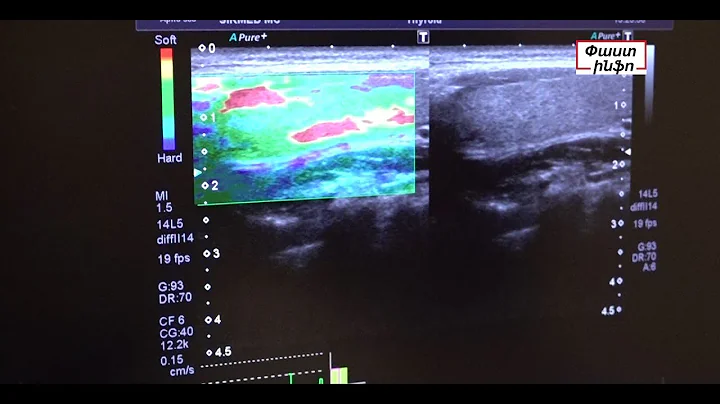

Վահանաձև գեղձը ստուգելու 10 պատճառ

Ներկայացնում է Հայկ Բլբուլյանը: Առողջությունը վտանգվում է, երբ ...